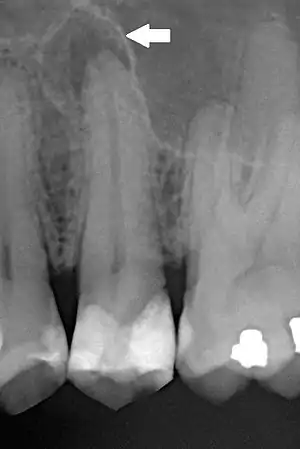

| Periapical dental radiograph showing chronic periapical periodontitis on the root of the left maxillary second premolar. Note large restoration present in the tooth, which will have undergone pulpal necrosis at some point before the development of this lesion. | |

The radiographic features of periapical inflammatory lesions vary depending on the time course of the lesion. Because very early lesions may not show any radiographic changes, diagnosis of these lesions relies solely on the clinical symptoms. More chronic lesions may show lytic (radiolucent) or sclerotic (radiopaque) changes, or both.